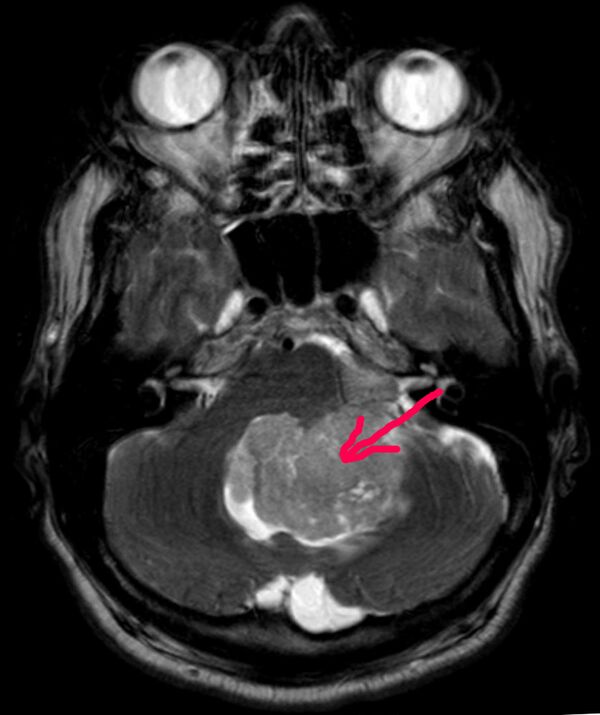

Магнитно-резонансная томограмма эпендимомы IV желудочка. Аксиальная проекция, Т2 режим. Новообразование выделено красным

В типичных случаях на МРТ эпендимомы видны в виде объёмных образований, которые заполняют, а иногда и полностью тампонируют полость IV желудочка и распространяются в большую затылочную цистерну или боковую цистерну моста. Солидная часть новообразования на Т1-взвешенных томограммах выглядит изо- или даже гипоинтенсивной и гиперинтенсивной на Т2-взвешенных томограммах[24].

Дифференциальная диагностика эпендимом с другими глиомами основывается в основном на их локализации и топографии, а не на различиях интенсивности сигнала или степени контрастного усиления[25]. Кистозный компонент имеет гипоинтенсивный сигнал на Т1-взвешенных МРТ и гиперинтенсивный по отношению к мозгу на изображениях, взвешенных по Т2. Гетерогенность структуры опухоли обусловлена наличием кист, петрификатов, опухолевой сосудистой сети. После введения контраста отмечается негомогенное усиление средней интенсивности[26]. Дифференциальную диагностику эпендимом боковых желудочков необходимо проводить с медуллобластомами и астроцитомами[23].